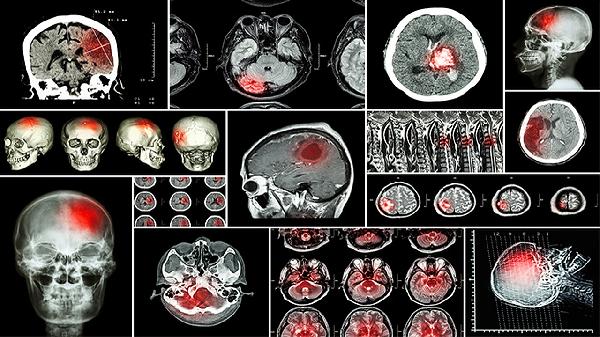

CT扫描对颅内感染的检出能力与感染类型和病程阶段相关。细菌性脑膜炎在CT上可能表现为脑膜强化或脑水肿;脑脓肿可见环形强化病灶伴周围水肿带;病毒性脑炎早期可能无异常,后期可显示颞叶低密度影。但结核性脑膜炎、隐球菌性脑膜炎等感染早期CT上可能无特异性表现。对于疑似颅内压增高患者,CT能快速排除占位性病变或脑疝风险,为腰椎穿刺提供安全评估。新型多排螺旋CT对微小病灶的检出率有所提升,但仍可能漏诊早期或轻度感染。